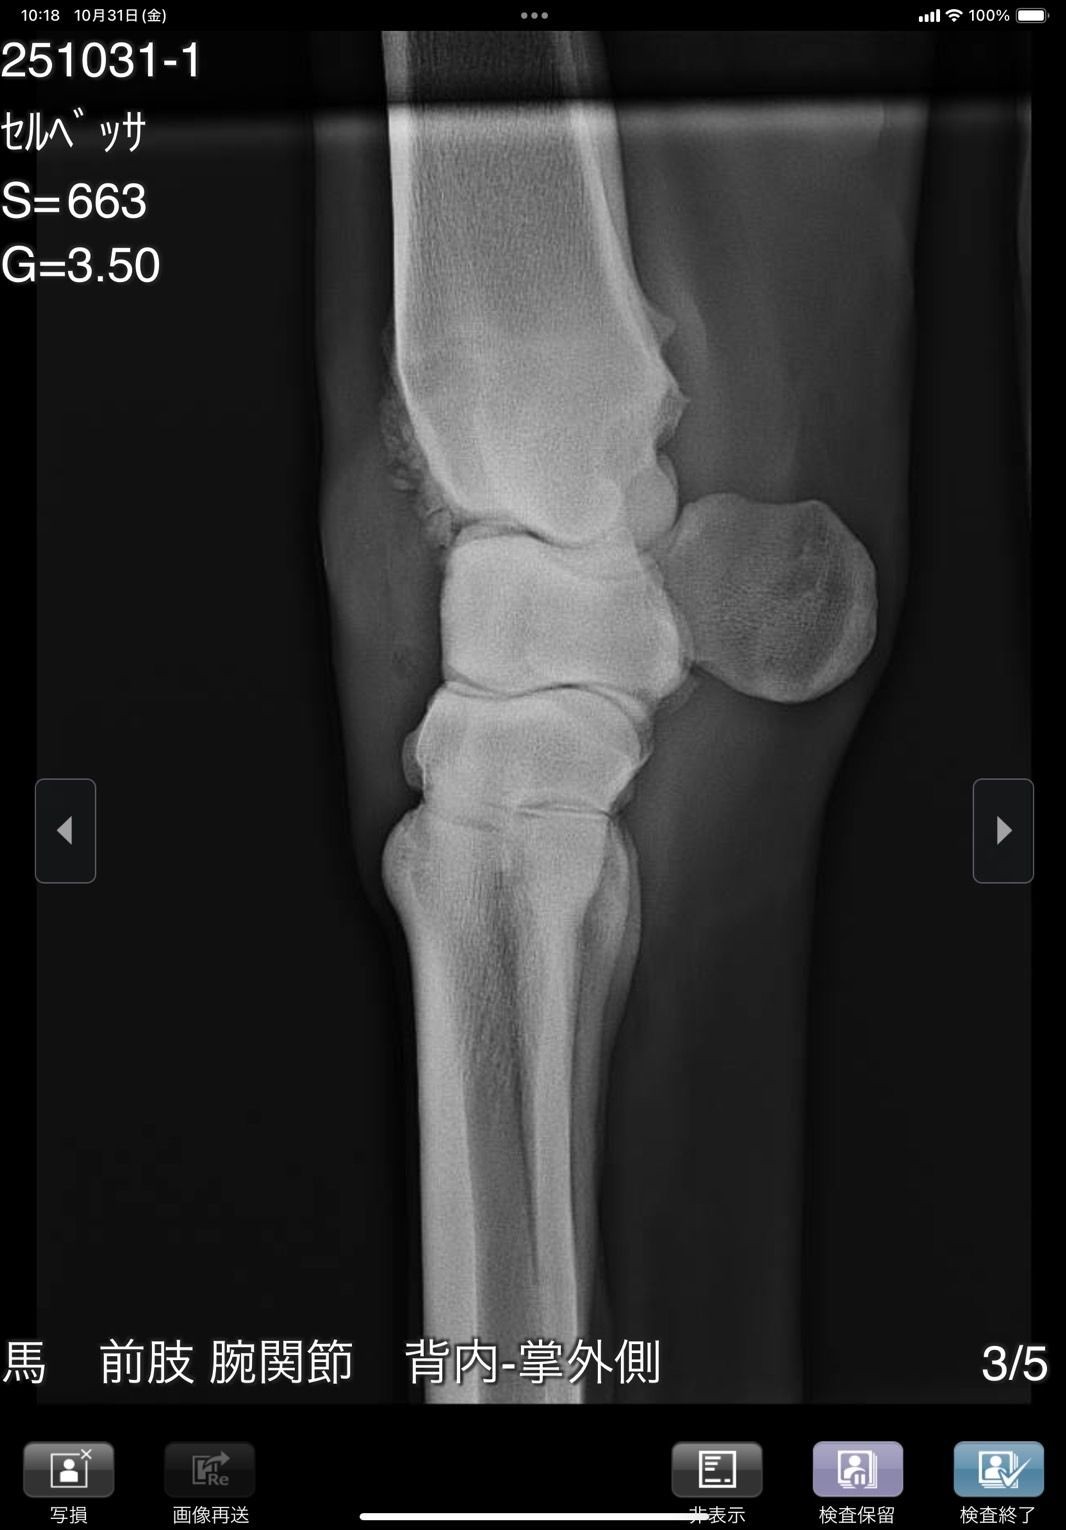

前肢が外向しているためか1歳秋の育成段階で右前に骨瘤ができ、中々固まらずに育成も遅れ、デビューは3歳4月となりました。デビュー後は4ヶ月で6戦を消化し比較的順調に出走できましたが、8/28の出走後にC3級への降級を狙って休養へ。帰厩に向けて乗りこんでいる所でしたが、10/31の調教後に右前膝に違和感があり、レントゲン検査を実施した所、骨片の剥離が見られました。その段階では大きな跛行は見られなかったためしばらく様子を見ましたが、速い調教を行うと歩様に違和感が出るため、手術が必要と考えられます。骨片除去手術を行いますと一定期間の休養が必要となるため、この度オークションへの出品とさせて頂きました。骨片除去手術は必要になると思いますが、元々の戦績からすると園田C2級で勝ち負け出来る能力があり、休養中にC3級への降級となりますので、適切な治療と休養をして頂ければ勝負になる可能性は高いと思います。骨折の状況については8/31撮影のレントゲン画像をご確認ください。

※10月31日の調教後に右前膝に違和感があり、レントゲン検査を行った所、骨片の剥離が見られました。